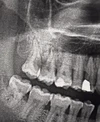

Diş X-Ray

Volumetrik Tomografi ile Tedavi Planlama

TÜRK TOPLUMUNDAKİ MANDİBULA VE MAKSİLLADAKİ 1. VE 2. PREMOLAR VE MOLAR DİŞLERİN YAKINDAKİ ÖNEMLİ ANATOMİK İLİŞKİSİNİN CONE BEAM COMPUTED TOMOGRAPHY İLE RETROSPEKTİF OLARAK DEĞERLENDİRİLMESİ-2018